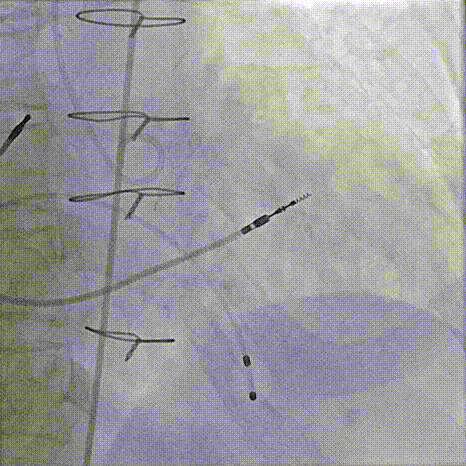

主动脉根部造影

80%工作位评估